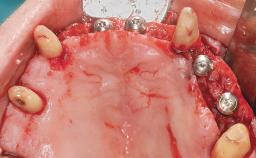

Immediate Loading of Six Implants in the Maxilla and Final Restoration with a Full-Arch CAD/CAM Zirconia FDP

# of Implants 6

Type of Implants One-Piece

Modality 6+ implants with immediate loading